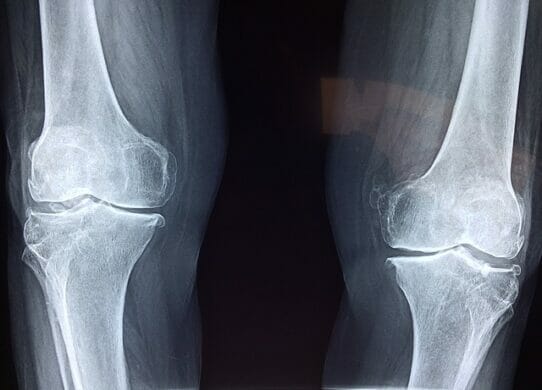

Il ginocchio è un’articolazione importantissima del nostro corpo perché ne consente il movimento, la deambulazione e ne sorregge, assieme alla caviglia e al…

Il legamento crociato anteriore è uno dei quattro legamenti principali che rendono stabile il ginocchio. All’ interno del ginocchio ci sono due legamenti…